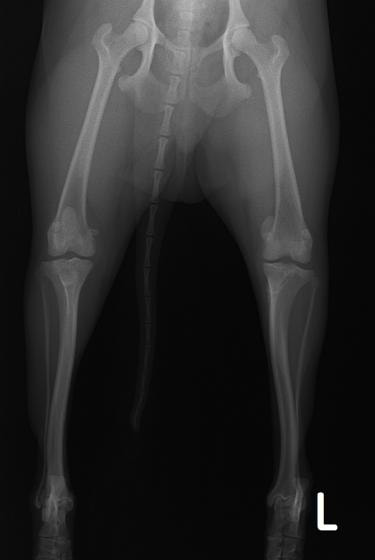

■ 症例24 キャバリア 7か月

左右膝蓋骨内方脱臼(左:グレードⅣ 右:グレードⅢ)

以前から左右後肢の跛行が認められ、整形外科学的検査・レントゲン検査により左右の膝蓋骨脱臼が認められた。症状が重度である左膝の膝蓋骨脱臼整復術を行った。外科手技は縫工筋及び内側広筋の解放、脛骨粗面の外側転位、滑車ブロック形造溝術、内外側関節方の縫縮を実施した。術後一か月時点で、左の膝蓋骨は安定しており経過は良好である。

本症例は成長期における重度の膝蓋骨脱臼であり、術後の再発の可能性もあるため、経過をしっかりと観察していく必要がある。また、今回手術を実施していない右膝に関しても経過を観察し、手術を検討していくこととする。